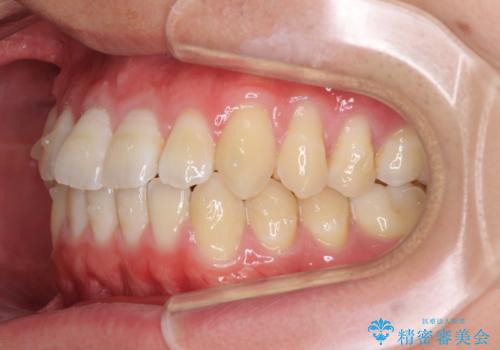

- 上下前歯のデコボコを気にして来院された患者様です。

叢生は軽微であり、費用を抑えて期間もあまりかけずに治療をしたいとのことで、インビザライン・ライトを用いて矯正治療を行うこととしました。

途中通院できなくなり、マウスピースの装着もしっかりとできなかったため、治療期間が長くかかってしまいました。